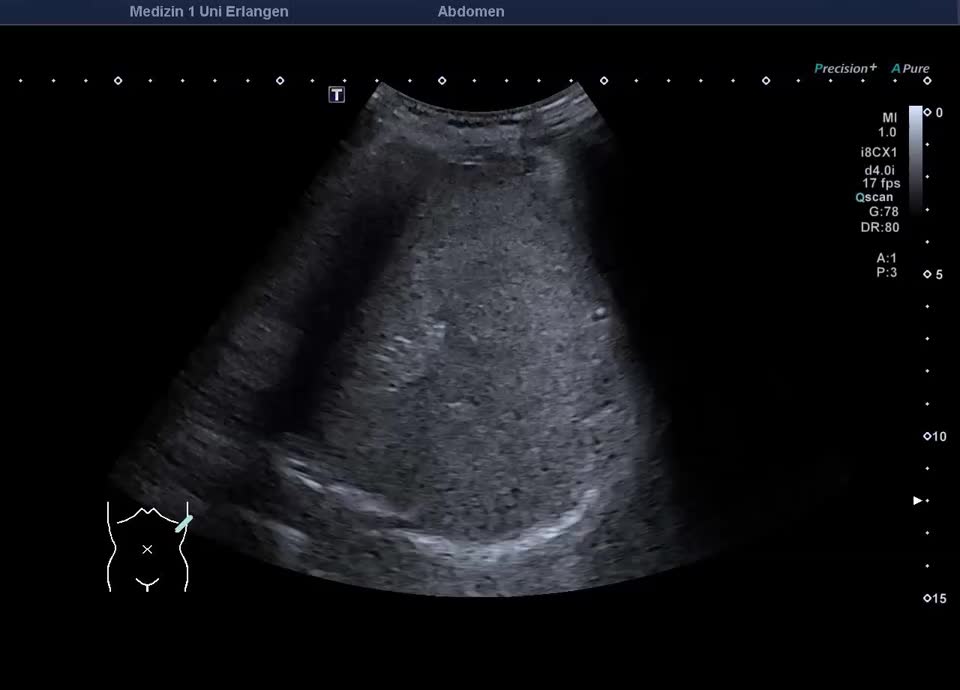

47-year-old patient presents to the emergency department with flank pain. Ultrasound shows a large, inhomogeneous, sharply defined mass in the left adrenal gland. A blood sample (including metanephrines) and a puncture (endosonographic access) are initiated for further clarification. Histologically adrenal cancer